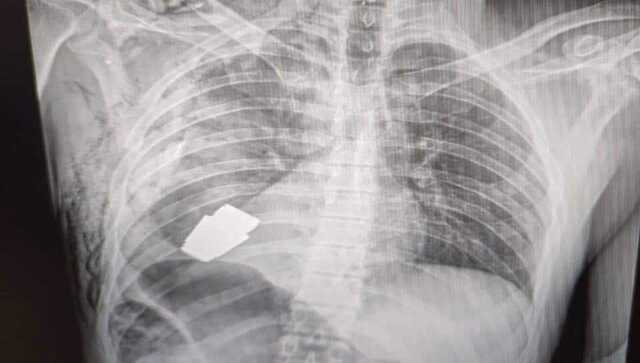

New Delhi: A Ukrainian soldier got a new lease of life when an unexploded VOG grenade was surgically removed from his Chest, just under his heart. Ukrainian army surgeons undertook the risky operation to the remove the still explosive grenade from the soldier body, with the help of two soldiers who looked over their safety. “Our military doctors conducted an operation to remove a VOG grenade, which did not break, from the body of a soldier.The operation lasted in the presence of two sappers who supervised the safety of the medical staff and the patient”, the General Staff of Ukrainian Armed Forces of Ukraine wrote on Facebook. Since the explosive was live and there were chances of an explosion, the doctors operated the soldier without electrocoagulation, a procedure that uses electric current to stop blood flow during the surgery. How did the grenade get into soldier’s chest? The Ukrainian military has not said anything about how the grenade got into the soldier’s chest. However, according to a New York Post report, the grenade was shot into the chest with a launcher. The VOG grenade is fired from an underbarrel launcher – small grenade launcher mounted just under the barrel of an assault rifle. These grenades explode when they hit something hard, but since it could pierce through the soldiers chest it didn’t explode and remained live, just underneath his heart, till it was very carefully removed. Read all the Latest News , Trending News , Cricket News , Bollywood News , India News and Entertainment News here. Follow us on Facebook, Twitter and Instagram.

Since the explosive was live and there were chances of an explosion, the doctors operated the soldier without electrocoagulation, a procedure that uses electric current to stop blood flow during the surgery